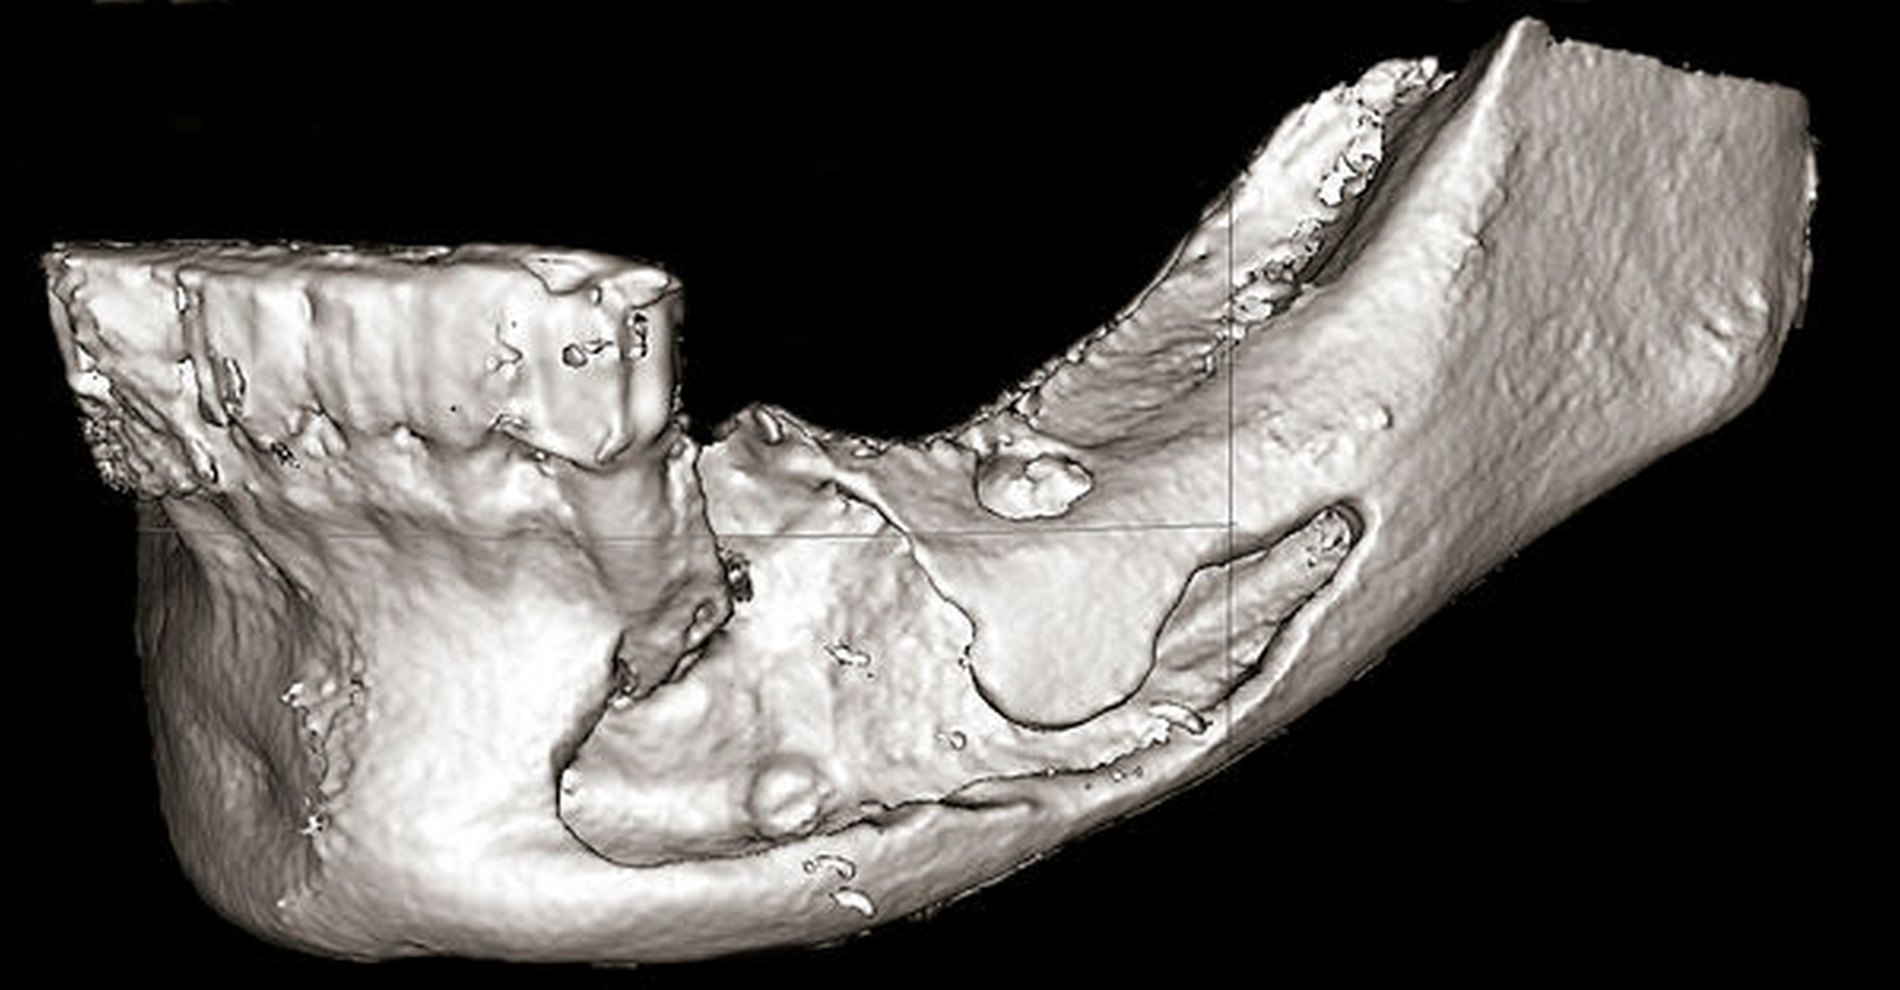

Zur Beurteilung der Überfüllung wurde alio loco eine DVT erstellt, die den Sealerverlauf in allen Ebenen abbildet. Der Austritt des Sealers nach lingual, nach bukkal und im Mandibularkanal wird hier dreidimensional präzise dargestellt (Abbildungen 3 und 4).

Auch im beschriebenen Fall wurde ein Sealer verwendet, der zwar nahezu kein Formaldehyd freisetzt, jedoch spielt eben auch das Ausmaß der Überstopfung und der damit entstandene Druck im Kanal eine entscheidende Rolle für die Nervschädigung [Tyagi et al., 2013]. Hier zeigt sich in der 3-D-Aufnahme insbesondere die Überfüllung mit Sealer in der zahnnahen, lockeren Spongiosa, aber auch in die benachbarten Weichgewebe lingual und vestibulär. Fonsêca et al. berichten ebenfalls über die Möglichkeit einer Überfüllung mit temporärem Sealer in die Hart- und Weichgewebe und über eine Diffusion ins benachbarte venöse und lymphatische System [Fonsêca et al., 2009].

Ist es zu einer Überextension gekommen, ist eine sofortige dreidimensionale Bildgebung zur Beurteilung der in der Regel röntgenopaken Materialien zur detaillierten Diagnostik – inwieweit der Mandibularkanal betroffen ist – und zur chirurgischen Therapieplanung als sinnvoll einzustufen. Die Digitale Volumentomografie (DVT) bietet hierbei eine schnelle und im Vergleich zur Computertomografie strahlungsärmere Alternative mit genauer Darstellung in allen drei Ebenen im Vergleich zur Panoramaschichtaufnahme [Bianchi et al., 2017; Gambarini et al., 2011; Tsompanides et al., 2014].